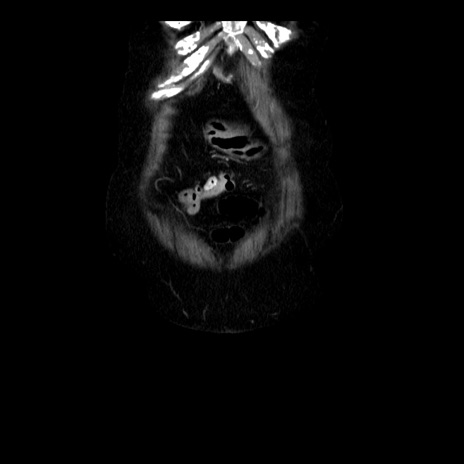

横断像